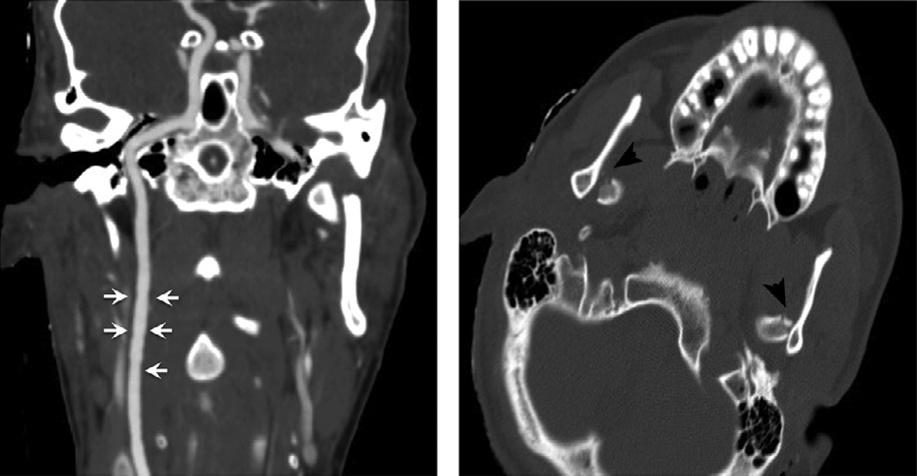

Fig.1.9. Coronalandsagittalreformattedimagescanmitigate volumeaveragingandstreakartifactsfromadjacentbony structures,improvingtheconspicuityofsubtlehemorrhage comparedtothatofthick-sliceaxialimagesalone.

Fig.1.10. Subtleinternalcarotidintimalirregularity(arrows) causedbyblunttrauma,withbilateraldisplacedmandibular condylefractures(arrowheads).